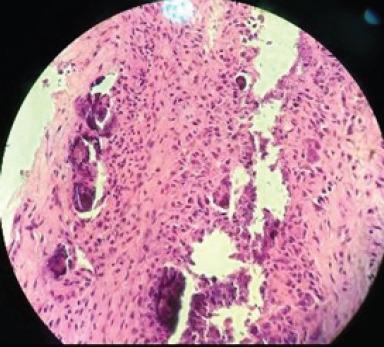

A 39-year-old female (right hand dominant) presented with the left elbow pain for the past 1 year. The diagnosis was achieved by radiography and confirmed by histopathology. Her pain did not respond to conservative treatment of analgesics, physiotherapy, and elbow support and a local steroid injection. She, therefore, underwent surgical exploration of the elbow, under general anesthesia. There was white-colored paste like a collection within the common extensor tendon origin, with dystrophic calcification of the tendon. The histology of the excised tissue revealed focal nodular aggregates of plump fibroblasts and osteoclastic giant cells around microcalcific foci. Large areas of fibrosis and calcific nodular deposits seen suggestive of calcific tendonitis.

一名39岁女性(右手为优势手),过去1年出现左肘疼痛。通过X线摄影确诊,并经组织病理学证实。她的疼痛对镇痛药、物理治疗、肘部支撑以及局部类固醇注射等保守治疗均无反应。因此,她在全身麻醉下接受了肘部手术探查。在伸肌总腱起点处有白色膏状物质聚集,肌腱存在营养不良性钙化。切除组织的组织学检查显示,微钙化灶周围有丰满的成纤维细胞和破骨巨细胞形成的局灶性结节状聚集。可见大片纤维化和钙化结节沉积,提示钙化性肌腱炎。